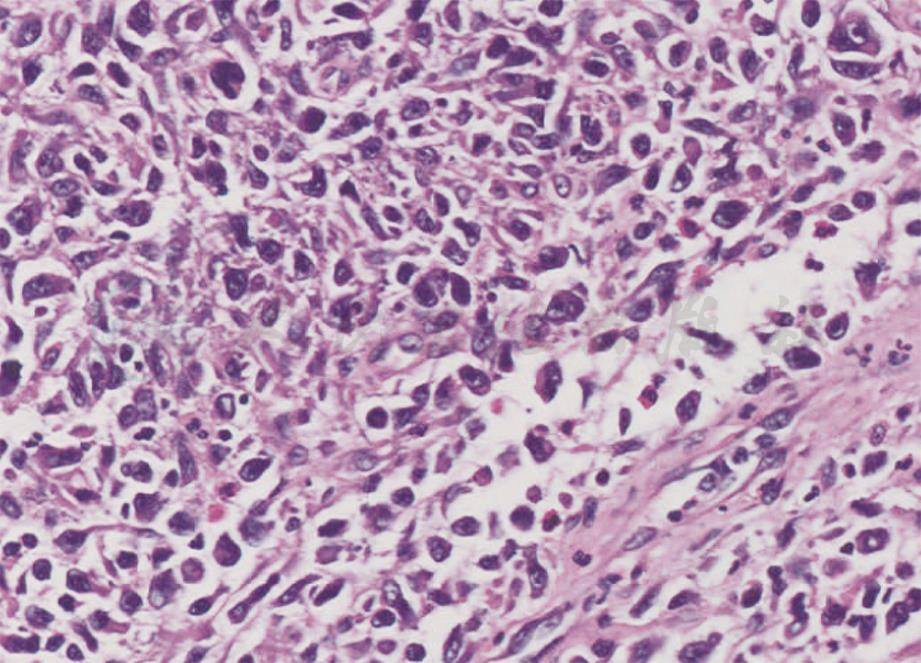

图2原发性皮肤间变性大细胞淋巴瘤组织病理表现

真皮内可见致密成片的大细胞浸润,部分细胞核异型性明显,还可见嗜酸性粒细胞(HE,200 ×)

特征为真皮致密细胞浸润,表皮受累少见,浸润的细胞由成片粘连的大CD30+肿瘤细胞组成(图2),细胞呈圆形或多形性,胞质丰富,嗜酸性,马蹄形胞核,核仁明显。肿瘤周围可见反应性淋巴细胞、组织细胞、嗜酸性粒细胞和中性粒细胞,溃疡性损害可见表皮增生。